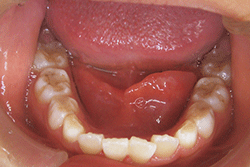

a:左側口底部に腫脹が見られる

b:左側ワルトン管の開口部付近に黄色の腫脹が見られる

図❶ a、b 初診時の口腔内写真

口腔内所見:左側口底部に20㎜程度の発赤を伴うび漫性腫脹を認め、唾液腺開口部付近の粘膜下に、わずかに黄色を呈する粟粒大の硬固物を認めた(図❶)。